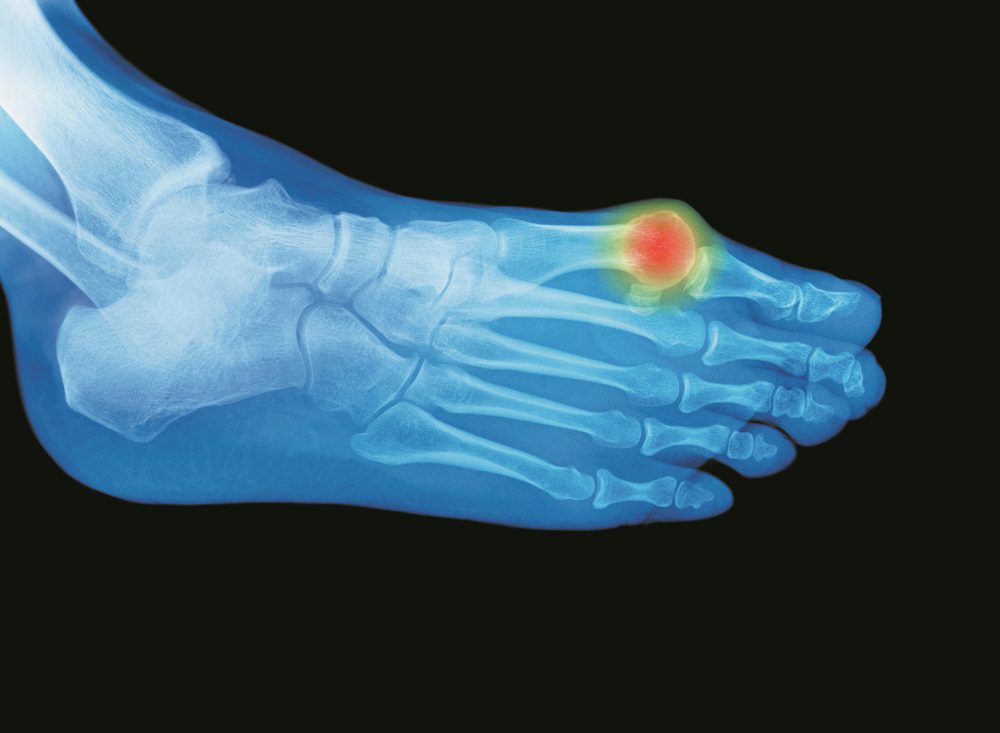

A slightly goofy word that connotes pain and deformity, bunion is derived from the Greek word for turnip. It’s a bony bump growing out from the side of one’s big toe. Bunions happen at the metatarsophalangeal joint, where the first long bone of the foot meets the first bone of the big toe.

Bunions are common: Approximately 30 percent of people ages 18 to 65 have them, and the prevalence increases with age. More than 70 percent of the elderly have them. They are more common in women than in men.